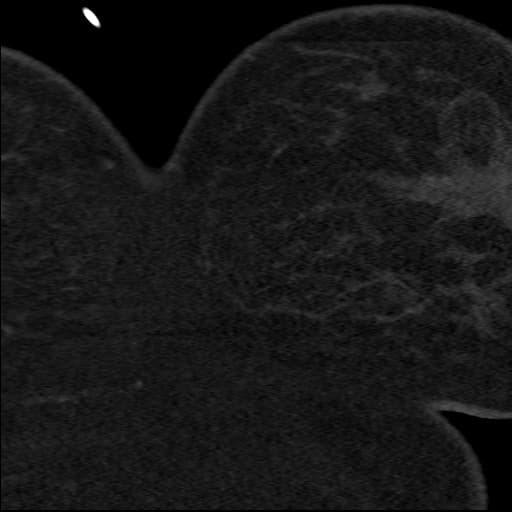

- Ống động mạch còn ống (patent ductus arteriosus), dạng kéo dài (elongated type), có hình ảnh thuốc cản quang đổ vào thân động mạch phổi giãn vừa (shunt trái sang phải - left to right shunt).

- Nhĩ trái giãn, kèm dày vách liên thuỳ và dày quanh phế quản - mạch máu, phù hợp với phù do tim nhẹ (mild cardiogenic edema).